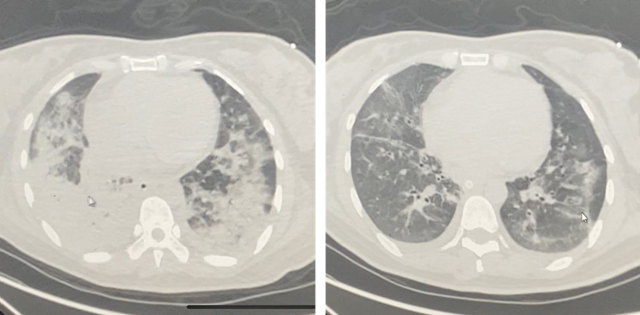

↑CT检查提示患者双肺大面积炎症,白色部分已丧失正常气体交换功能

CT提示患者双肺重度肺炎,大面积弥漫性渗出,呈“大白肺”貌。

在经过持续五天的俯卧位通气治疗后,廖女士的病情有了显著改善,感染指标下降的同时,复查CT也提示“大白肺”重新变为“黑肺”,肺功能得以恢复,患者顺利脱离呼吸机拔除气管插管。